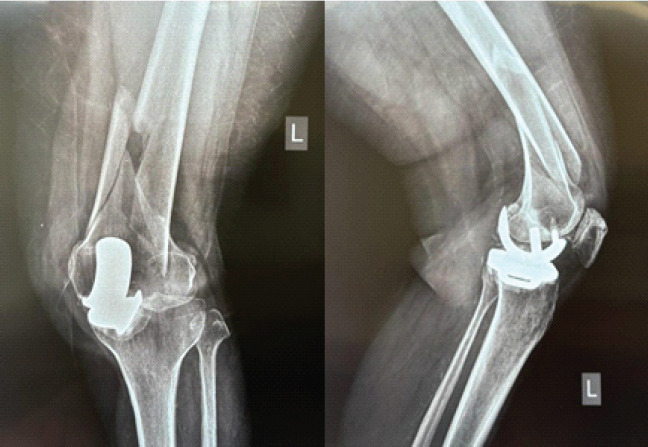

Case report: We present two unique cases of PPFs following cemented mobile-bearing Oxford UKA in elderly South Asian women. The first case involves a 63-year-old woman who sustained a high-energy supracondylar femoral PPF (Unified Classification System Type C) 9 months post-UKA. Despite the severity of the injury, radiographs confirmed the femoral component remained well-fixed with no evidence of polyethylene insert dislocation. She was treated successfully with retrograde intramedullary nailing, achieving full fracture union and 130° of knee flexion by 6 months postoperatively. The second case involves a 60-year-old woman who sustained a proximal third tibial PPF (Type C) two and a half months after UKA. Again, both components remained secure without signs of loosening. She was treated with locking plate fixation, resulting in complete union and full independent ambulation by 6 months. Both patients remained clinically well at 2.5 years of follow-up, with intact UKA components and no functional limitations.